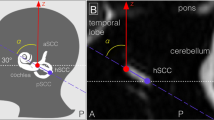

Functional images were obtained in a clinical 3 Tesla MRI scanner (Skyra, Siemens, Germany) with a 64-channel array head and neck coil employing echo-planar imaging (EPI) with a fast T2* weighted gradient-echo sequence (TR= 500 ms, multi-band factor 6, 30 continuous axial slices covering the brainstem and the cerebellum, 2.5 mm isotropic voxels, field of view 210 mm2, TE= 34.8 ms, posterior-to-anterior phase encoding direction to minimize distortions in the brainstem regions of interest) modified for optimal infratentorial neuroimaging. A high-resolution T1-weighted MP-RAGE sequence was acquired in sagittal orientation (TR = 2060 ms\TE = 2.17 ms, flip angle = 12°, FoV = 240 mm, slice thickness = 0.75 mm, A-P phase encoding, 0.75 mm in-plane resolution, GRAPPA factor 2) for DARTEL-based normalization including geodesic shooting to MNI space during the subsequent preprocessing.